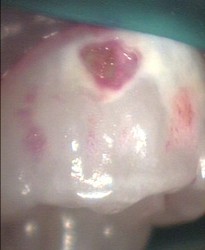

massive plaque build up disclosing 'red' tablet

immediate cleaning